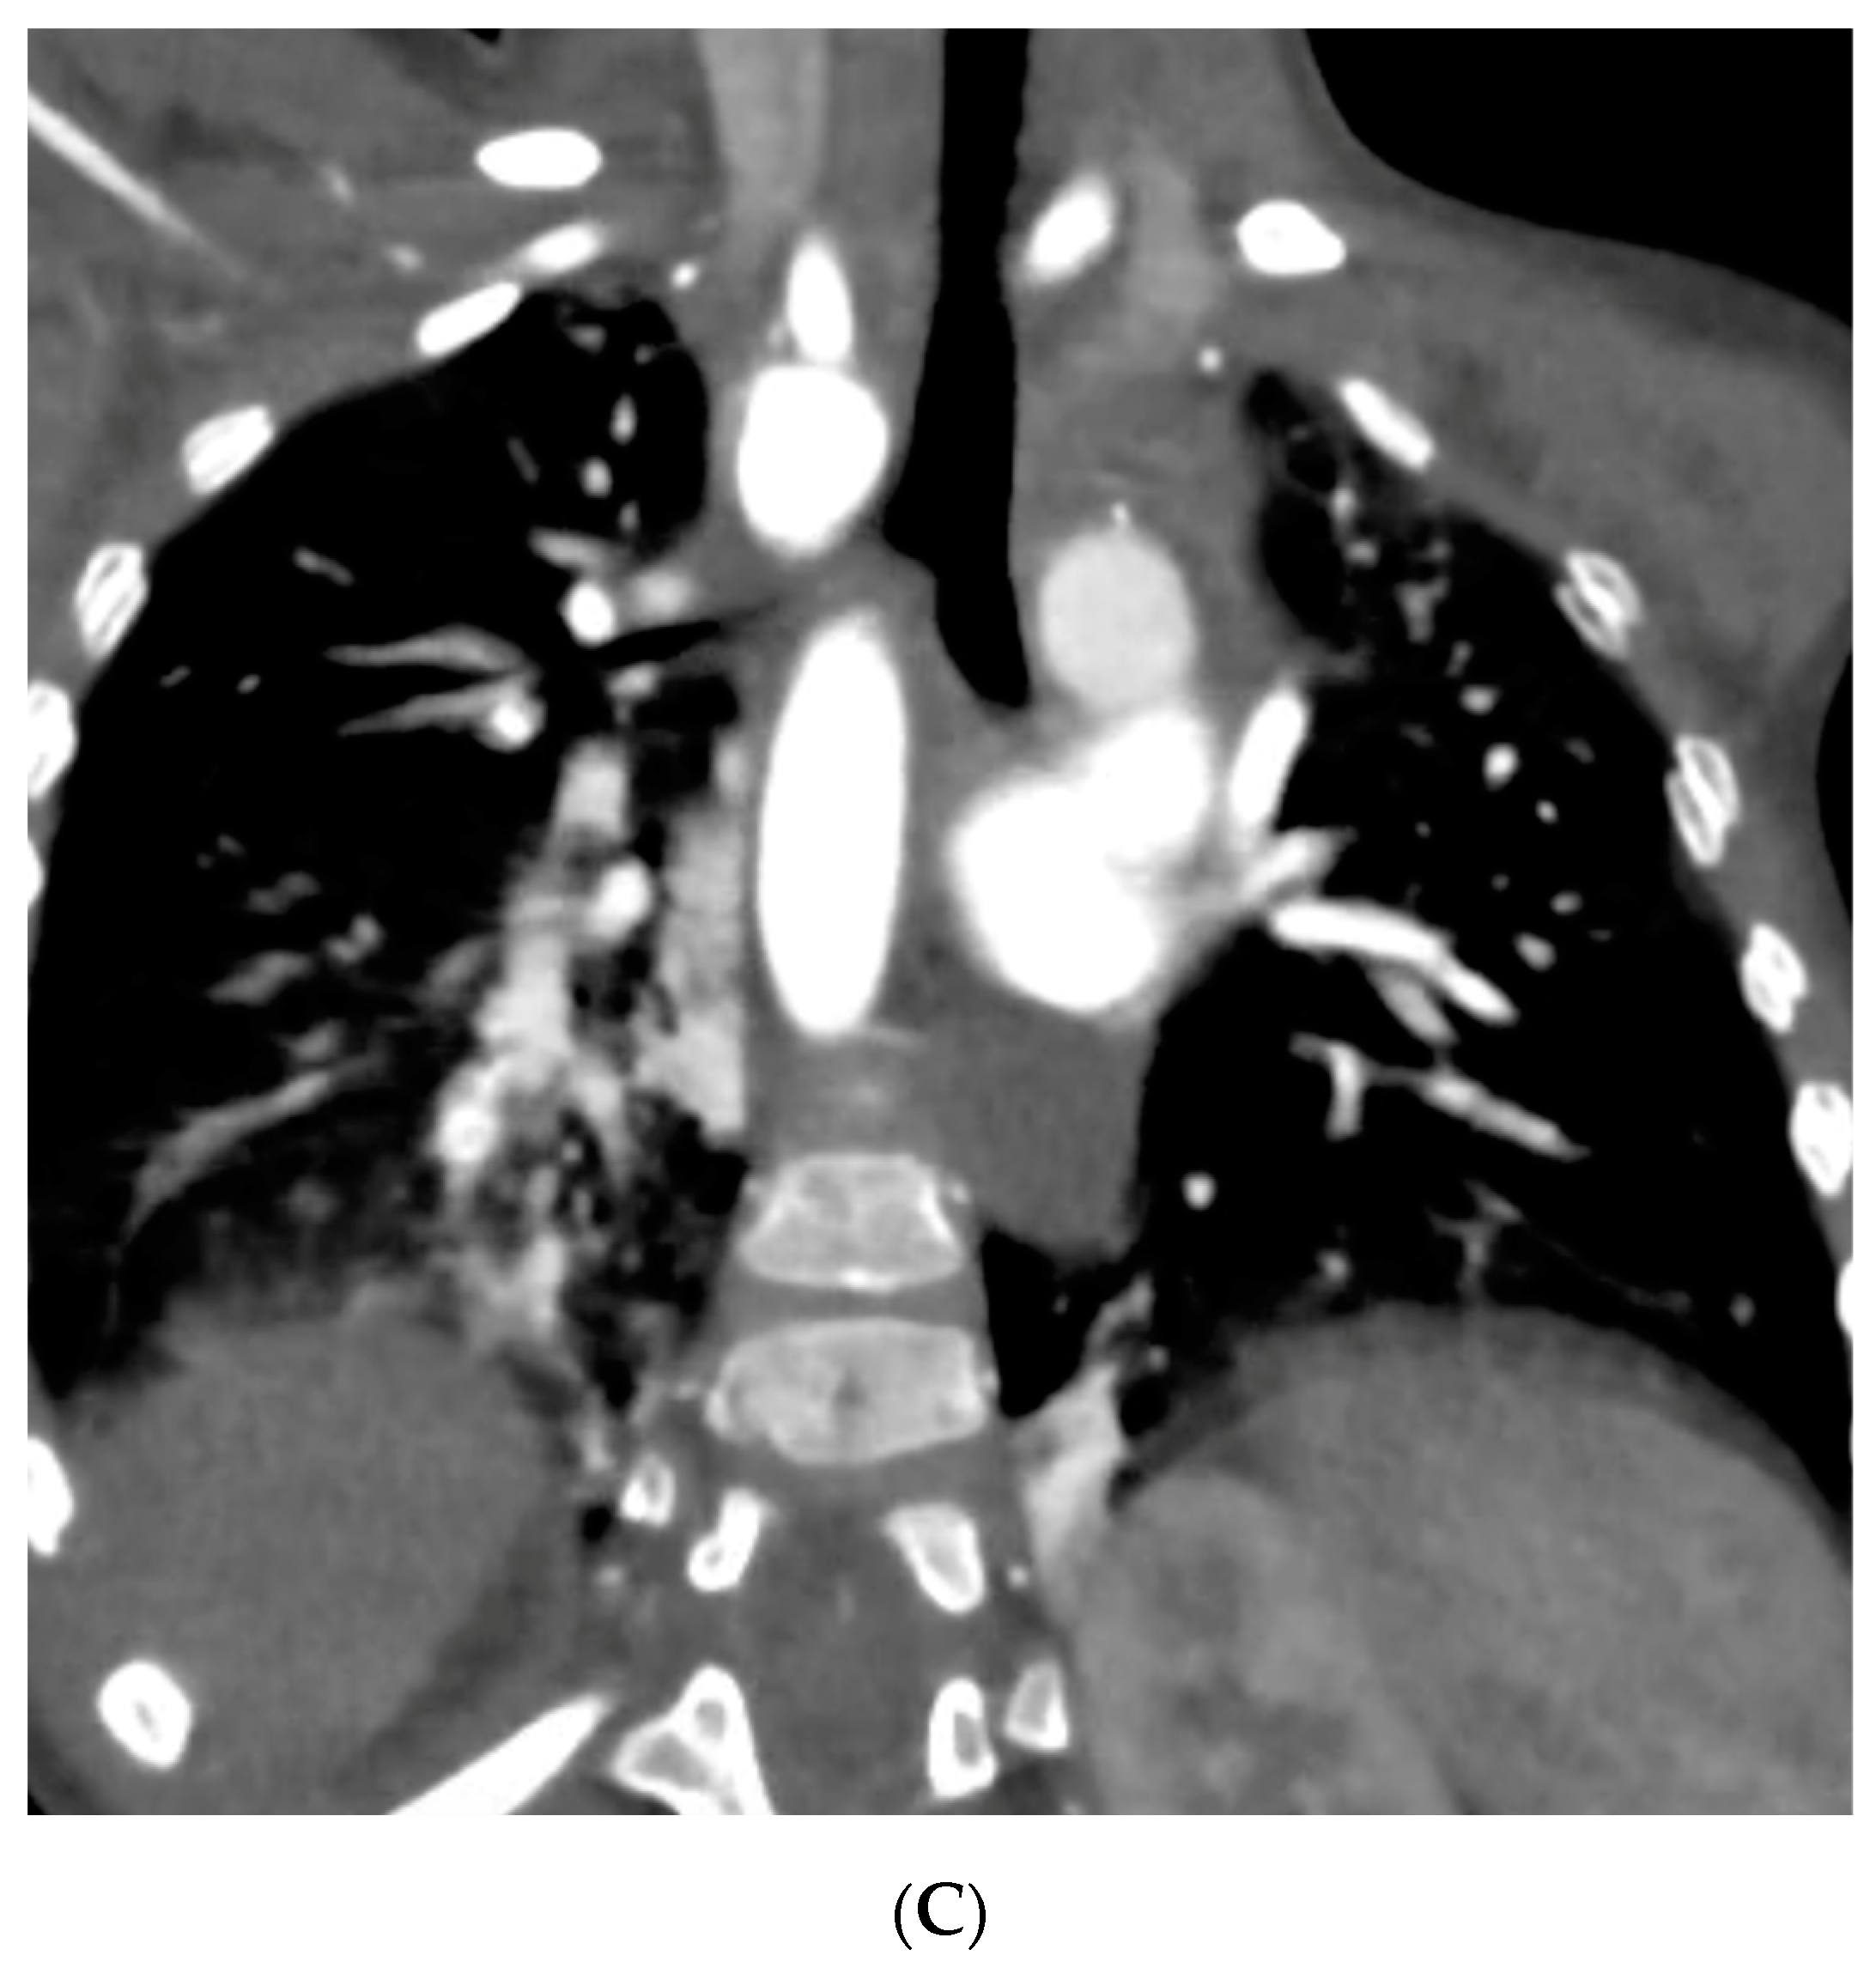

The patient was then placed on a gastrostomy tube and followed up until 14 months of age, showing persistent dysphagia and weighing 8.2 kg. Hence, the decision was made to perform a surgical repair of the vascular ring. Prior to the surgical incision, an endoscopic and EndoFLIPTM evaluation were conducted, demonstrating an esophageal narrowing at the level of the vascular ring and an abnormal increase in esophageal impedance, respectively. A limited left posterior thoracotomy was performed, allowing the visualization of a left-sided esophagus with a RAA originating from behind, and an aberrant LSA exiting from a KD. The LLA, which was observed compressing the esophagus, was divided. The KD was obliterated, with two purse-string sutures, and the aberrant LSA was dissected and divided from the aorta, then re-implanted into the left carotid artery (LCA) via an end-to-side anastomosis. Following the closure of the chest, another endoscopic evaluation and EndoFLIPTM assessment were performed, which evidenced an improvement in esophageal narrowing and impedance, respectively. The patient’s recovery was uneventful, and she was discharged on postoperative day 4. Follow-up visits demonstrated symptomatic improvement without postoperative complications, and she was meeting her growth milestones. A recent CTA performed 2 years post-procedure revealed a patent re-implanted LSA into the LCA and no tracheal deformities (Figure 3) (Supplementary Material Video S2–S4).

Figure 3.

Postoperative Computed Tomography Angiography. (A) Three-dimensional reconstruction showing the RAA status post KD plication and LSA re-implantation into the LCA, evidencing patency of the re-implanted artery and an outpouching of the KD’s remnant with a surgical clip at the distal end. (B) Coronal view demonstrating esophageal displacement without evident narrowing. (C) Coronal view evidencing no tracheal deformities.